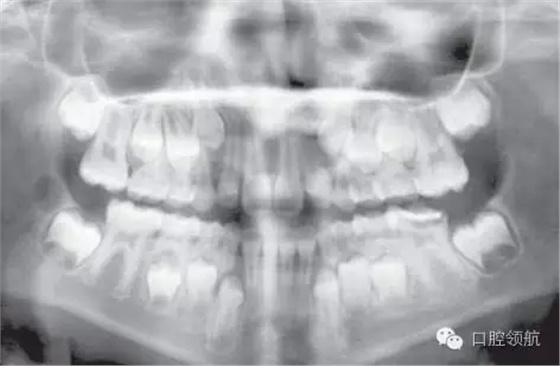

這是一個(gè)全科牙醫(yī)轉(zhuǎn)診的病例。該名女性患者I類錯(cuò)牙合,輕度擁擠,LL6嚴(yán)重齲壞,無法保留。患牙有間歇性的夜間痛,使其在夜間痛醒。圖2.8是由全科牙醫(yī)提供的最近的全景片。

圖2.8

全景片上最主要的特征有哪些?

● 混合牙列。

● 切牙已萌出。

● LL6嚴(yán)重齲壞;可見遠(yuǎn)中根根周感染,有臨時(shí)修復(fù)體存在。

● 除第三磨牙以外所有恒牙都存在(LR8可見早期牙胚發(fā)育)。

● 第二磨牙的牙冠發(fā)育完成。下頜的根間區(qū)域已開始發(fā)育。